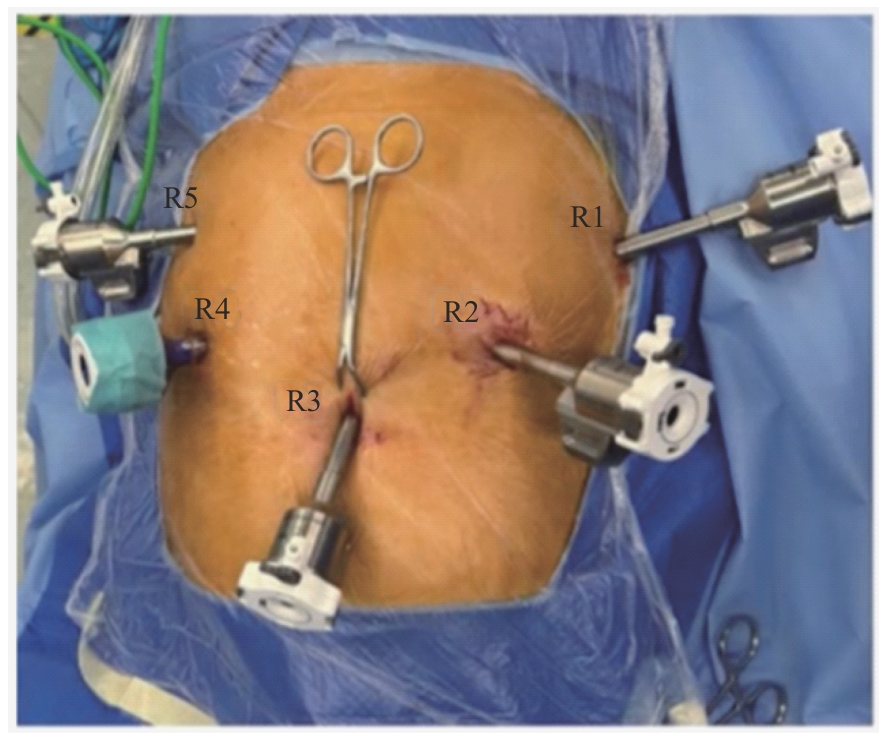

目的·比较分析机器人与腹腔镜辅助近端胃切除联合双肌瓣吻合术在治疗早期胃上部癌中的安全性及近期效果。方法·采用回顾性队列研究方法,分析2023年9月至2024年3月于上海交通大学医学院附属仁济医院胃肠外科行近端胃切除联合双肌瓣吻合进行消化道重建的31例早期胃癌患者临床病理资料。根据手术方式不同,将患者分为机器人辅助手术组(机器人组,20例)和腹腔镜辅助手术组(腹腔镜组,11例)。比较2组患者的一般临床资料、术中情况及术后恢复情况。术后6个月随访时,行上消化道造影和食管胃镜检查,判断是否有吻合口狭窄及反流性食管炎;同时,使用欧洲癌症研究与治疗组织(European Organization for Research and Treatment of Cancer,EORTC)的胃癌特异模块量表(Quality of Life Questionnaire-Stomach 22,QLQ-STO22)评估患者的生活质量。结果·2组患者的一般资料,包括性别、年龄、术前合并症、美国麻醉医师协会(American Society of Anesthesiologists,ASA)分级、Siewert分型以及肿瘤的病理分期,差异均无统计学意义(均P>0.05)。2组患者均顺利完成手术,无中转开腹。机器人组的胃食管吻合时间较腹腔镜组显著缩短[(31.09±8.23)min vs (43.73±8.83)min,P<0.001],而术中及术后各项指标,包括手术时间、术中失血量、淋巴结清扫数、术后胃管留置时间、术后流质饮食开始时间、术后住院天数以及术后并发症发生率在2组之间差异均无统计学意义(均P>0.05)。术后6个月随访共有30例患者完成(其中机器人组失访1例)。上消化道造影及食管胃镜检查结果显示,仅腹腔镜组1例患者出现吻合口狭窄,机器人组出现A级和B级反流性食管炎各1例,腹腔镜组出现B级反流性食管炎1例。2组反流性食管炎和吻合口狭窄发生率差异均无统计学意义(均P>0.05)。EORTC QLQ-STO22评分结果显示,机器人组在吞咽困难、胃食管反流、饮食受限3个维度的评分,以及量表总分均显著低于腹腔镜组(均P<0.05)。结论·机器人辅助近端胃切除联合双肌瓣吻合手术安全可行,术中吻合时间更短,且在术后功能恢复和患者生活质量提升方面具有潜在优势。

Objective ·To compare the safety and short-term outcomes of robot-assisted versus laparoscopic-assisted proximal gastrectomy combined with double-flap esophagogastrostomy in the treatment of early upper gastric cancer. Methods ·A retrospective cohort study was conducted to analyze the clinical and pathological data of 31 early gastric cancer patients who underwent proximal gastrectomy combined with double-flap esophagogastrostomy for gastrointestinal reconstruction at the Department of Gastrointestinal Surgery, Renji Hospital, Shanghai Jiao Tong University School of Medicine, from September 2023 to March 2024. Based on the surgical approach, patients were divided into the robot-assisted surgery group (robotic group, 20 cases) and the laparoscope-assisted surgery group (laparoscopic group, 11 cases). General clinical data, intraoperative conditions, and postoperative recovery between the two groups were compared. At the 6-month postoperative follow-up, upper gastrointestinal radiography and esophagogastroscopy were performed to assess anastomotic stricture and gastroesophageal reflux disease. Additionally, the gastric cancer-specific module of the European Organization for Research and Treatment of Cancer (EORTC), Quality of Life Questionnaire-Stomach 22 (QLQ-STO22), was used to evaluate the patients′ quality of life. Results ·The general data of the two groups, including gender, age, preoperative comorbidities, American Society of Anesthesiologists (ASA) classification, Siewert classification, and pathological staging of tumors, showed no statistically significant differences (all P>0.05). All patients successfully underwent the procedure without conversion to open surgery. The time for gastroesophageal anastomosis was significantly shorter in the robotic group compared to the laparoscopic group [(31.09±8.23) min vs (43.73±8.83) min, P<0.001], while there were no statistically significant differences in other intraoperative and postoperative parameters, including operative time, intraoperative blood loss, number of lymph nodes removed, duration of gastric tube placement, time to start a liquid diet, length of postoperative hospital stay, and incidence of postoperative complications (all P>0.05). At the 6-month postoperative follow-up, 30 patients completed the follow-up, with one patient lost to follow-up in the robotic group. Upper gastrointestinal radiography and esophagogastroscopy results showed that only one patient in the laparoscopic group developed an anastomotic stricture, while one patient in the robotic group developed grade A and one developed grade B gastroesophageal reflux disease (GERD). In addition, one patient in the laparoscopic group also developed grade B GERD. The incidences of GERD and anastomotic stricture showed no statistically significant differences between the two groups (both P>0.05). EORTC QLQ-STO22 results indicated that the robotic group had significantly lower scores in the dimensions of dysphagia, gastroesophageal reflux, and dietary restrictions, as well as in the total score, compared to the laparoscopic group (all P<0.05). Conclusion ·Robot-assisted proximal gastrectomy combined with double-flap esophagogastrostomy is safe and feasible. It shortens anastomosis time and offers potential advantages in postoperative functional recovery and quality of life improvement.